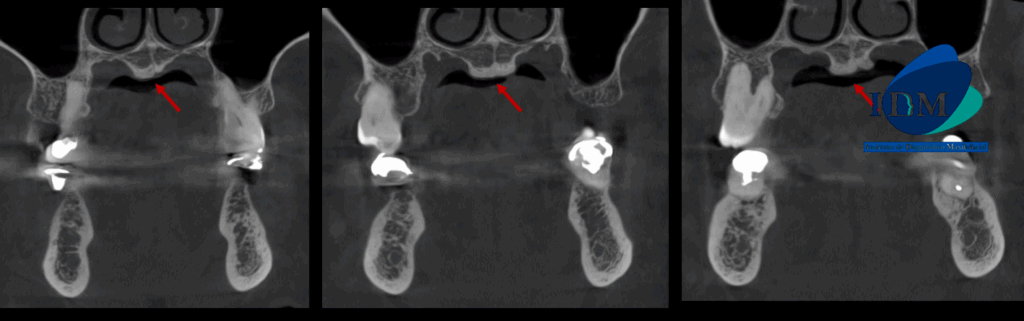

En la radiografía panorámica (Figura 1), se observa edentulismo parcial, múltiples restauraciones protésicas e implantes dentales. Además de un aumento de la densidad ósea en zona de paladar.

Radiografia Panorámica